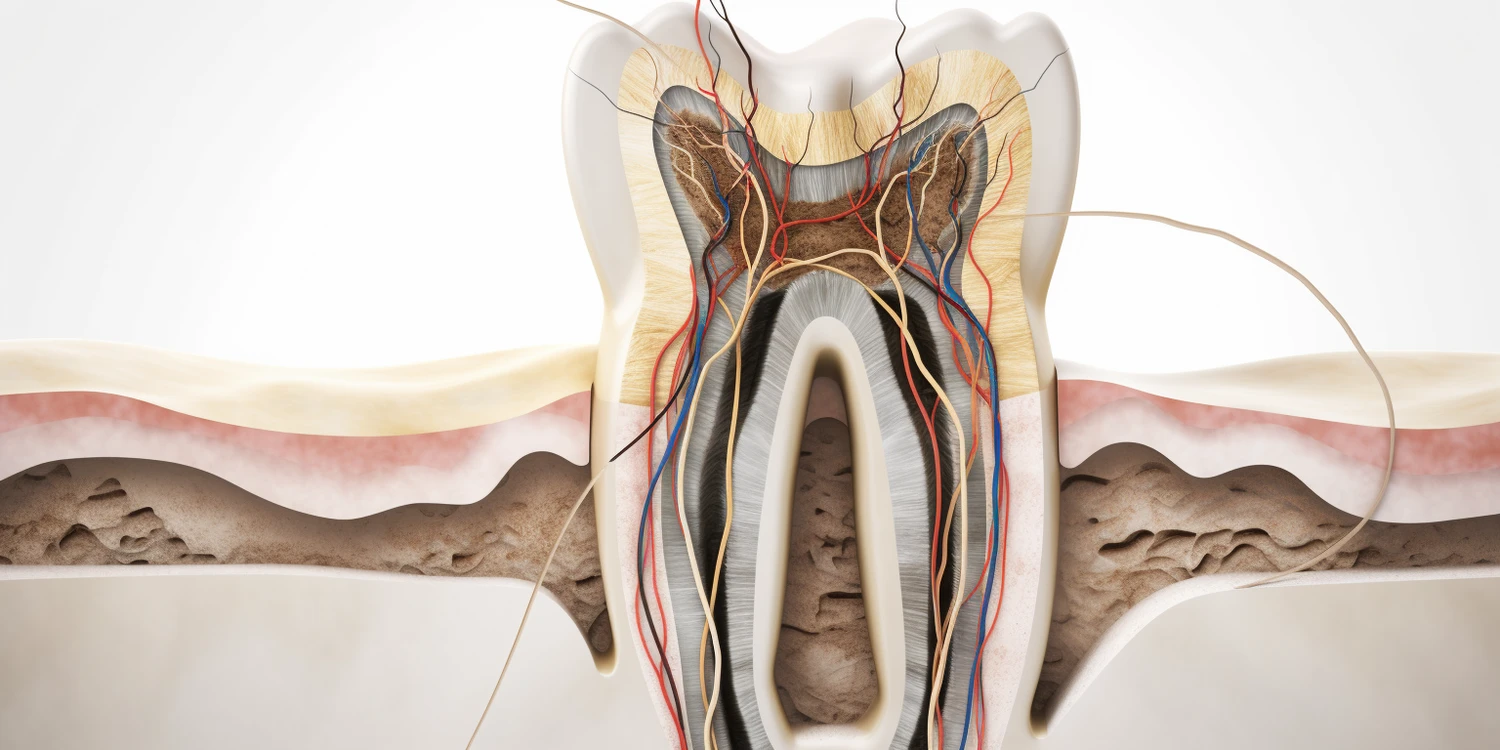

Problemy stomatologiczne u dorosłych mogą przybierać różne formy, a ich występowanie często związane jest z zaniedbaniami w zakresie higieny jamy ustnej oraz niezdrowym stylem życia. Jednym z najczęstszych problemów jest próchnica, która rozwija się w wyniku działania bakterii na resztki pokarmowe pozostające na zębach. Nieleczona próchnica może prowadzić do bólu zęba oraz konieczności przeprowadzenia bardziej skomplikowanych zabiegów, takich jak leczenie kanałowe. Kolejnym powszechnym problemem są choroby dziąseł, które mogą prowadzić do ich krwawienia, obrzęku oraz w skrajnych przypadkach utraty zębów. Osoby palące oraz te z cukrzycą są szczególnie narażone na rozwój tych schorzeń. Wśród innych problemów można wymienić nadwrażliwość zębów, która objawia się bólem podczas spożywania gorących lub zimnych napojów oraz jedzenia słodyczy. Zmiany w kolorze zębów również są częstym zjawiskiem, które może być wynikiem zarówno naturalnego procesu starzenia się, jak i wpływu diety czy używek.